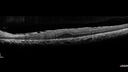

Bietti's Crystalline Dystrophy - CYP4V2 homomzygous

58-year-old-female (from Thailand)

Patient had evaluation for LASIK and there was concern that the BCVA was not normal.

PMHx Benign, Meds: none

VA 20/25 OU

IOP 16,14

Anterior segment: 1+ NS

Genetics homozygous CYP4V2